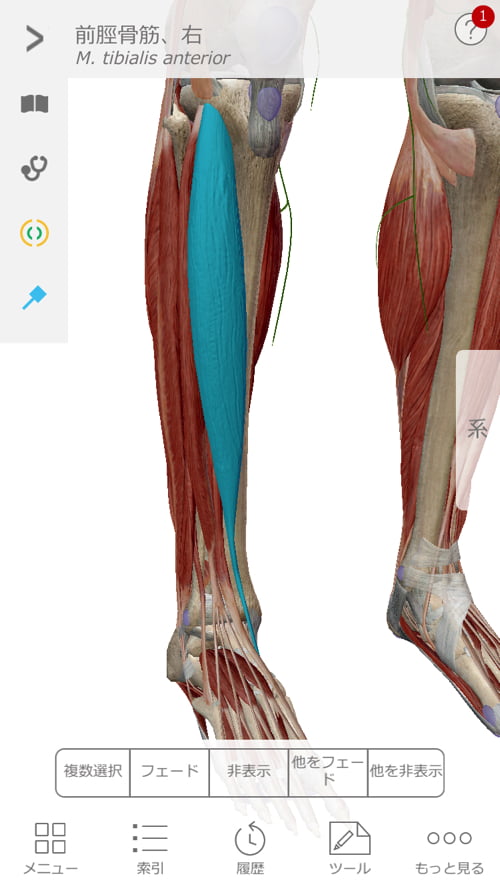

施術はまず足首から足の甲、そして膝へ繋がるこれらの筋肉や腱を調え直しました。

図で分かるように足の甲から膝へ、足裏から膝へと繋がっています。

そして膝から上は腰骨に繋がっているので、膝は足首にも腰にも影響があるのです。

そして腰の痛み。

脊柱管狭窄の部分を触っても軽く叩いても痛みが無いので

脊柱管狭窄と腰の痛みは直接の関係が無いという前提で

仙骨から鼠径部までの施術を丁寧に行いました。

整形外科で治らなかった脊柱管狭窄症の原因

痛みの原因はズバリ膝のヨジレ。

膝から鼠径部にかけての硬直と

太腿から臀部にかけての硬直が腰骨を引っ張ってしまい

骨盤を正しい位置からずらしてしまい

ズレた骨盤が神経に触れて痛かったのです。

腰の痛みは結果であって原因ではありません。

だから腰をいくら治しても治らないのです。